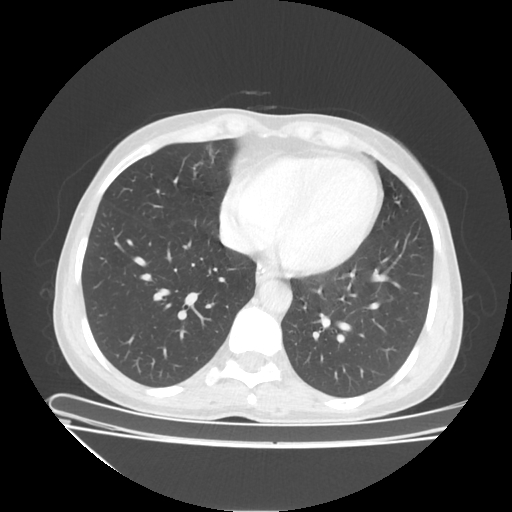

Original NATIVE CT scan (input)

No window - Raw intensity values

Lung window (WL -600, WW 1500 β†’ Low βˆ’1350, High +150)